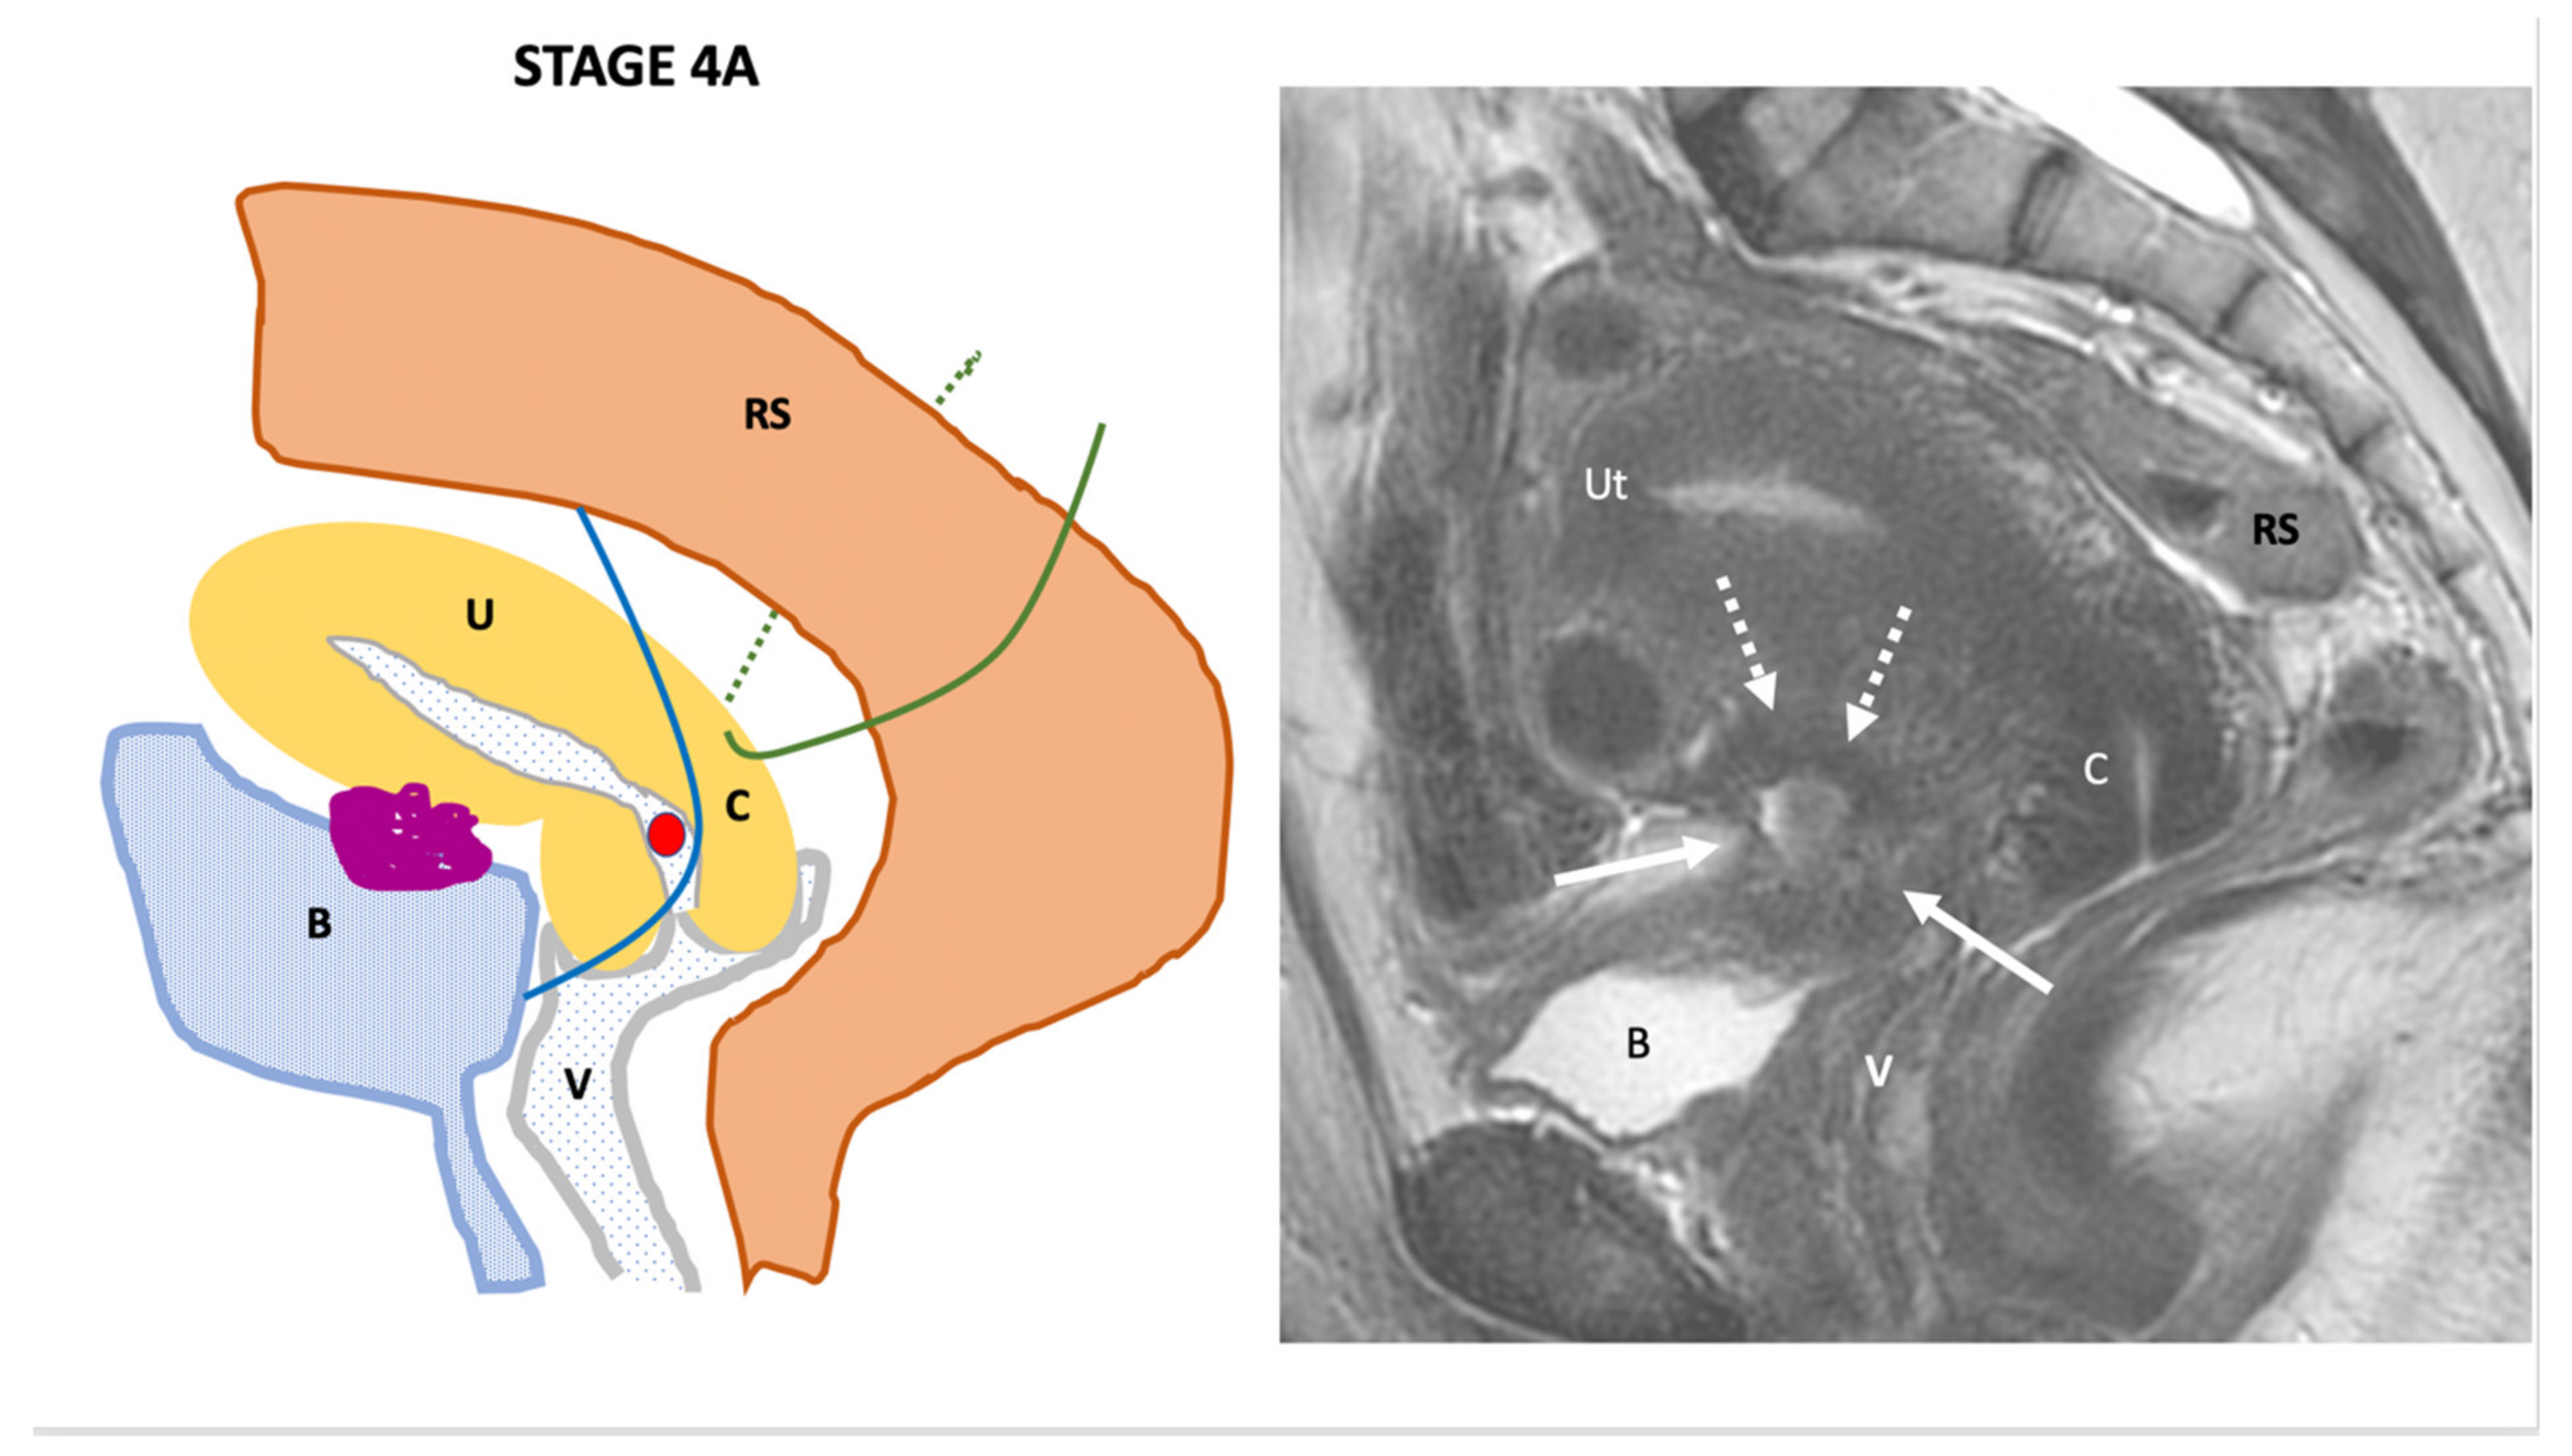

| Endo-Stage MRI IV | Endometriosis has involved the bladder or rectosigmoid colon |

| |